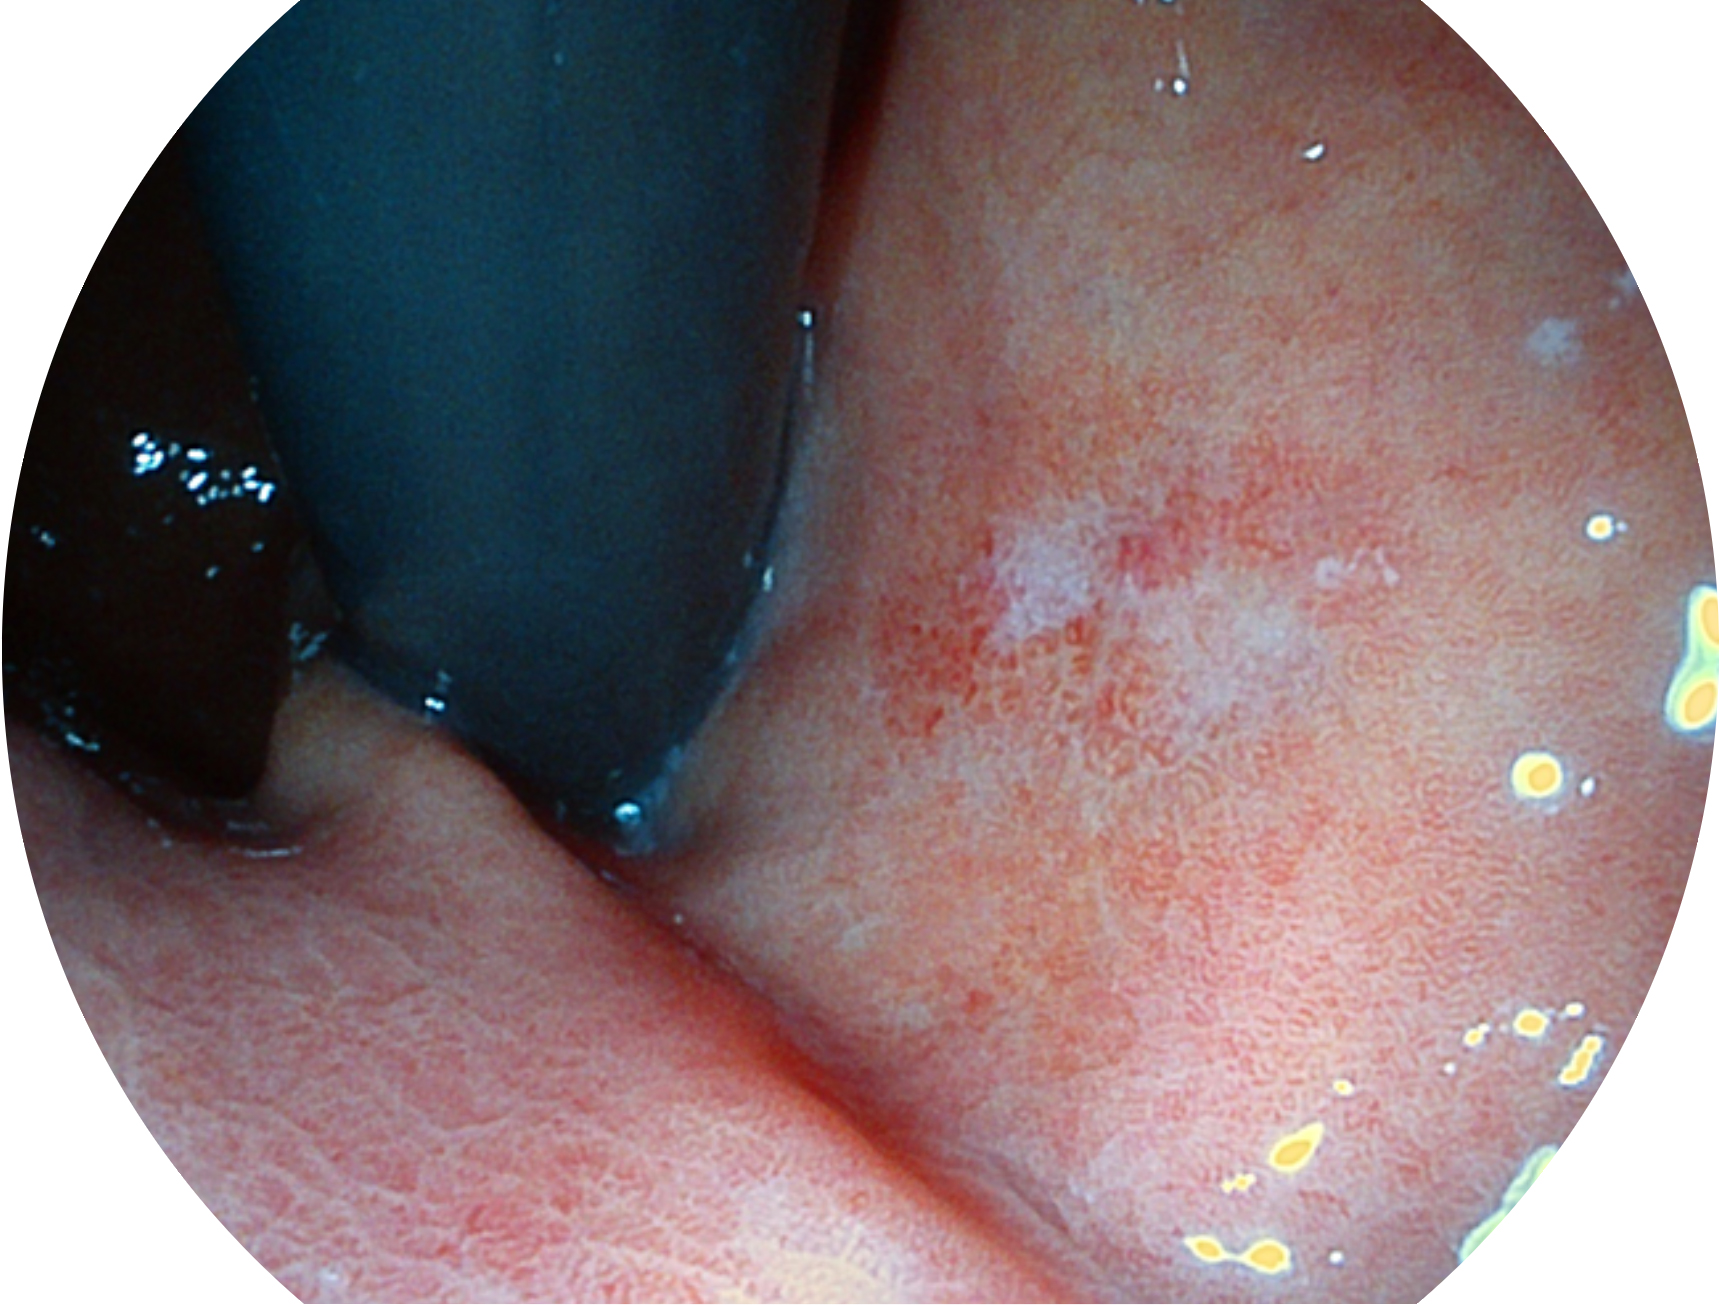

米兰官方网站新开发的内镜染色技术,主要是基于多波长LED 光源的开发,VLS-55Q 四波长LED 光源是由四个不同颜色的LED光按照相应照明模式所规定的特定发光比例进行合束后形成,合束后形成的照明光的光谱由红光、绿光、蓝光及蓝紫光这四个不同的波段范围构成。具有更高光谱自由度,通过光谱比例的控制,实现了聚谱成像技术,英文全称为“Spectral Focused Imaging, SFI”,缩写为“SFI”和光电复合染色成像技术,英文全称为“Versatile Intelligent Staining Technology, VIST”,缩写为“VIST”。